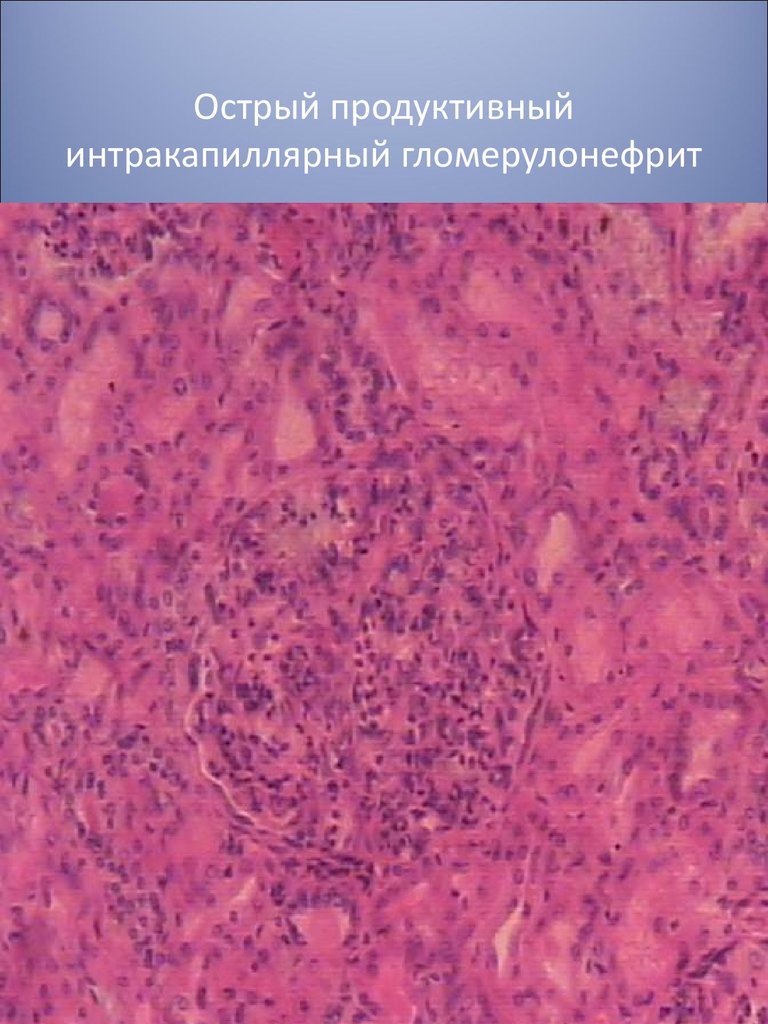

Механизм остро го диффузного гломерулонефрита